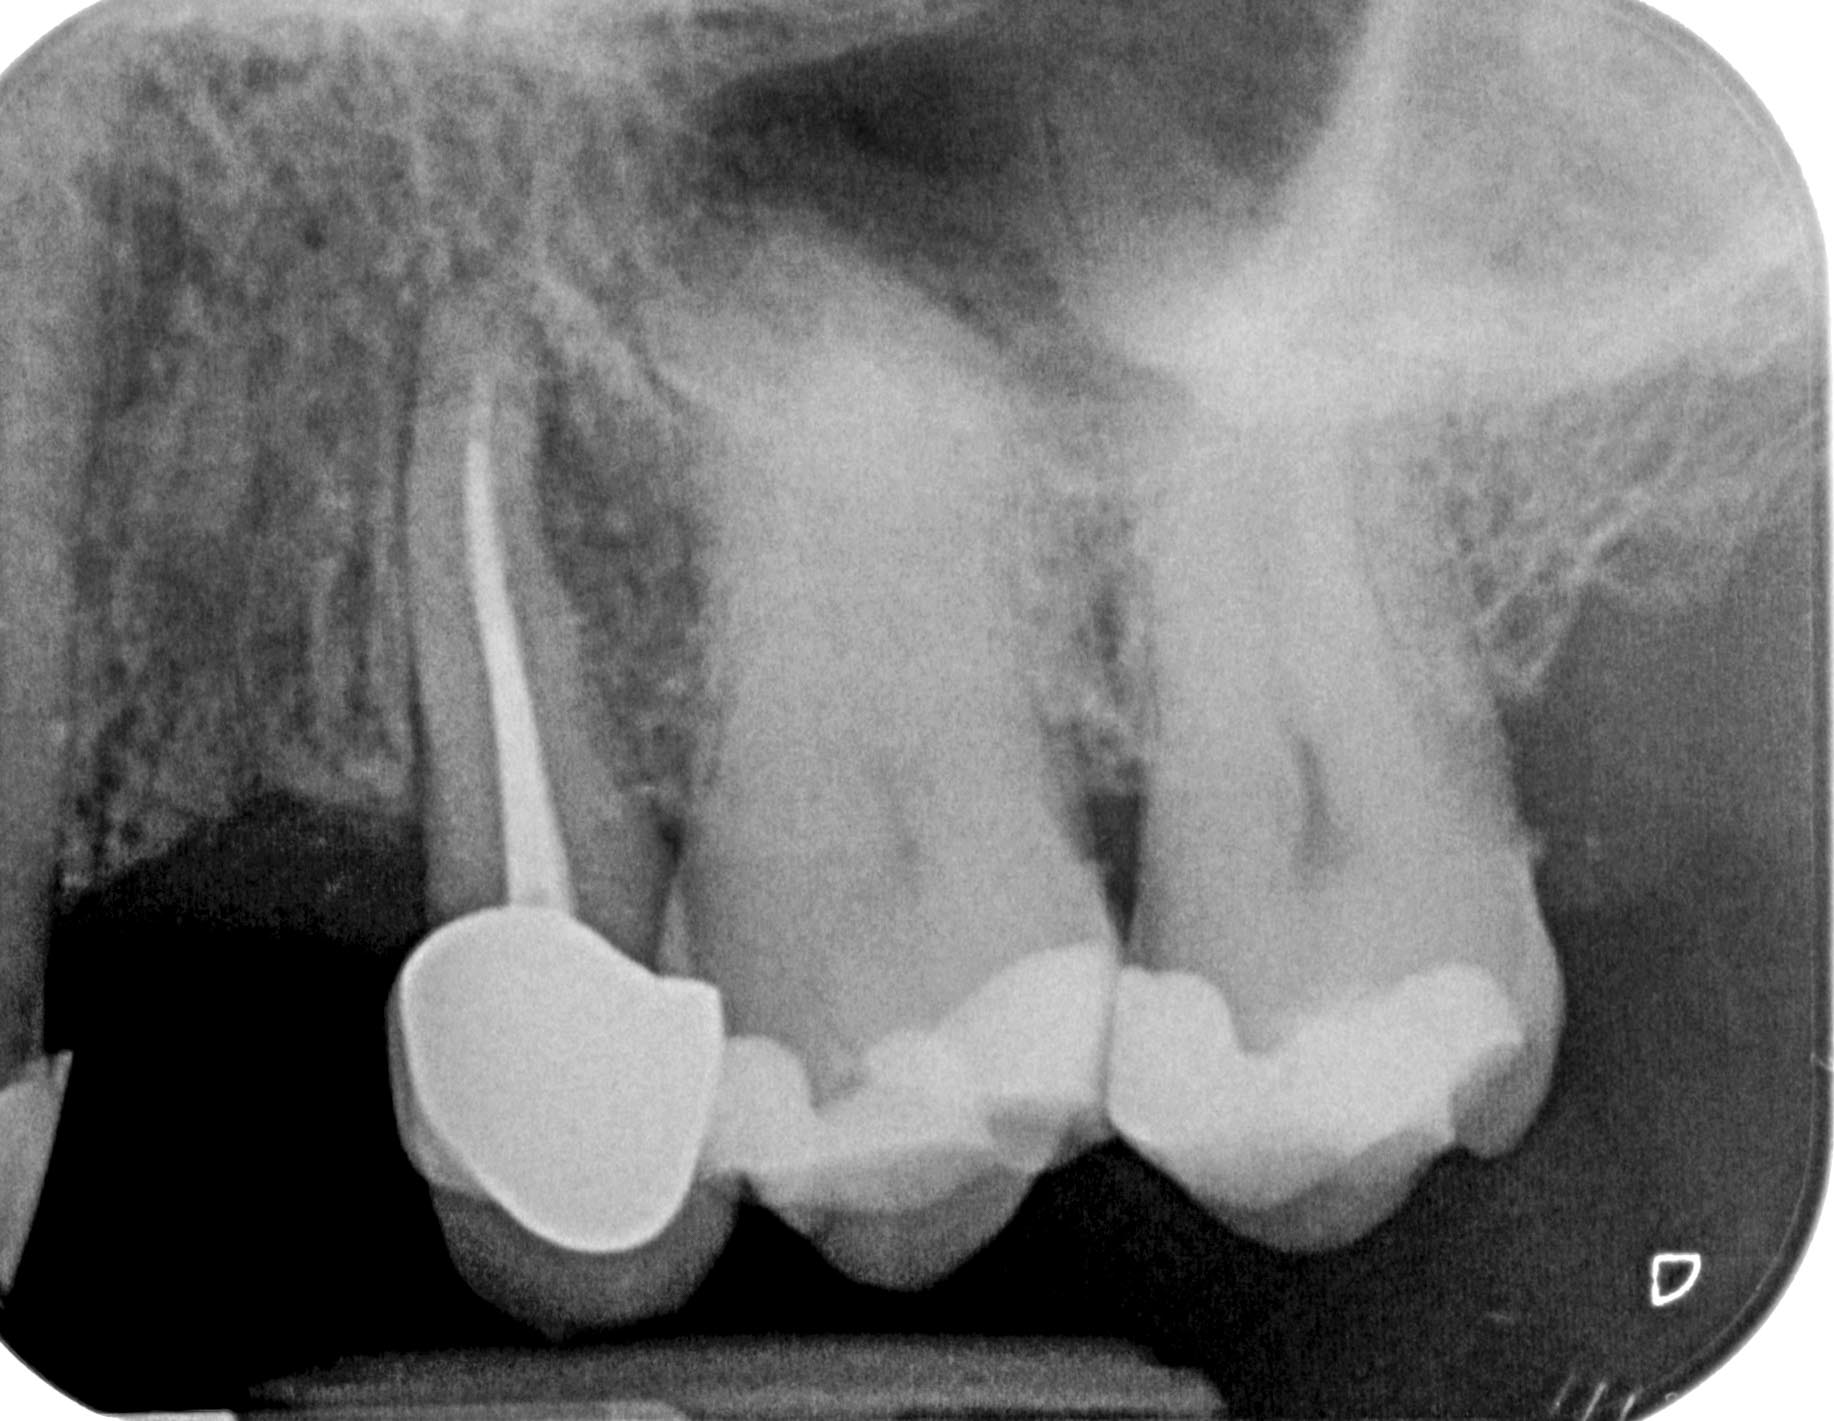

KM_25-1-3 Veröffentlicht 16. November 2015 am 1834 × 1421 in 5 Prämolaren (2) Zahn 25 vor WF Revision, aikale und laterale Aufhellung